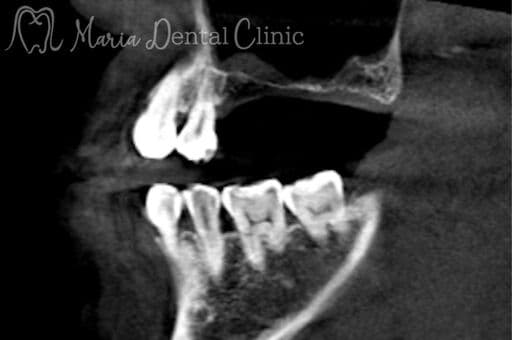

CT

3次元的に頭蓋骨の解剖学的形態を詳細に把握することで、インプラントの手術をより安全に行うための診断ツールです。現在、インプラント治療ではCT撮影は必須とされています。